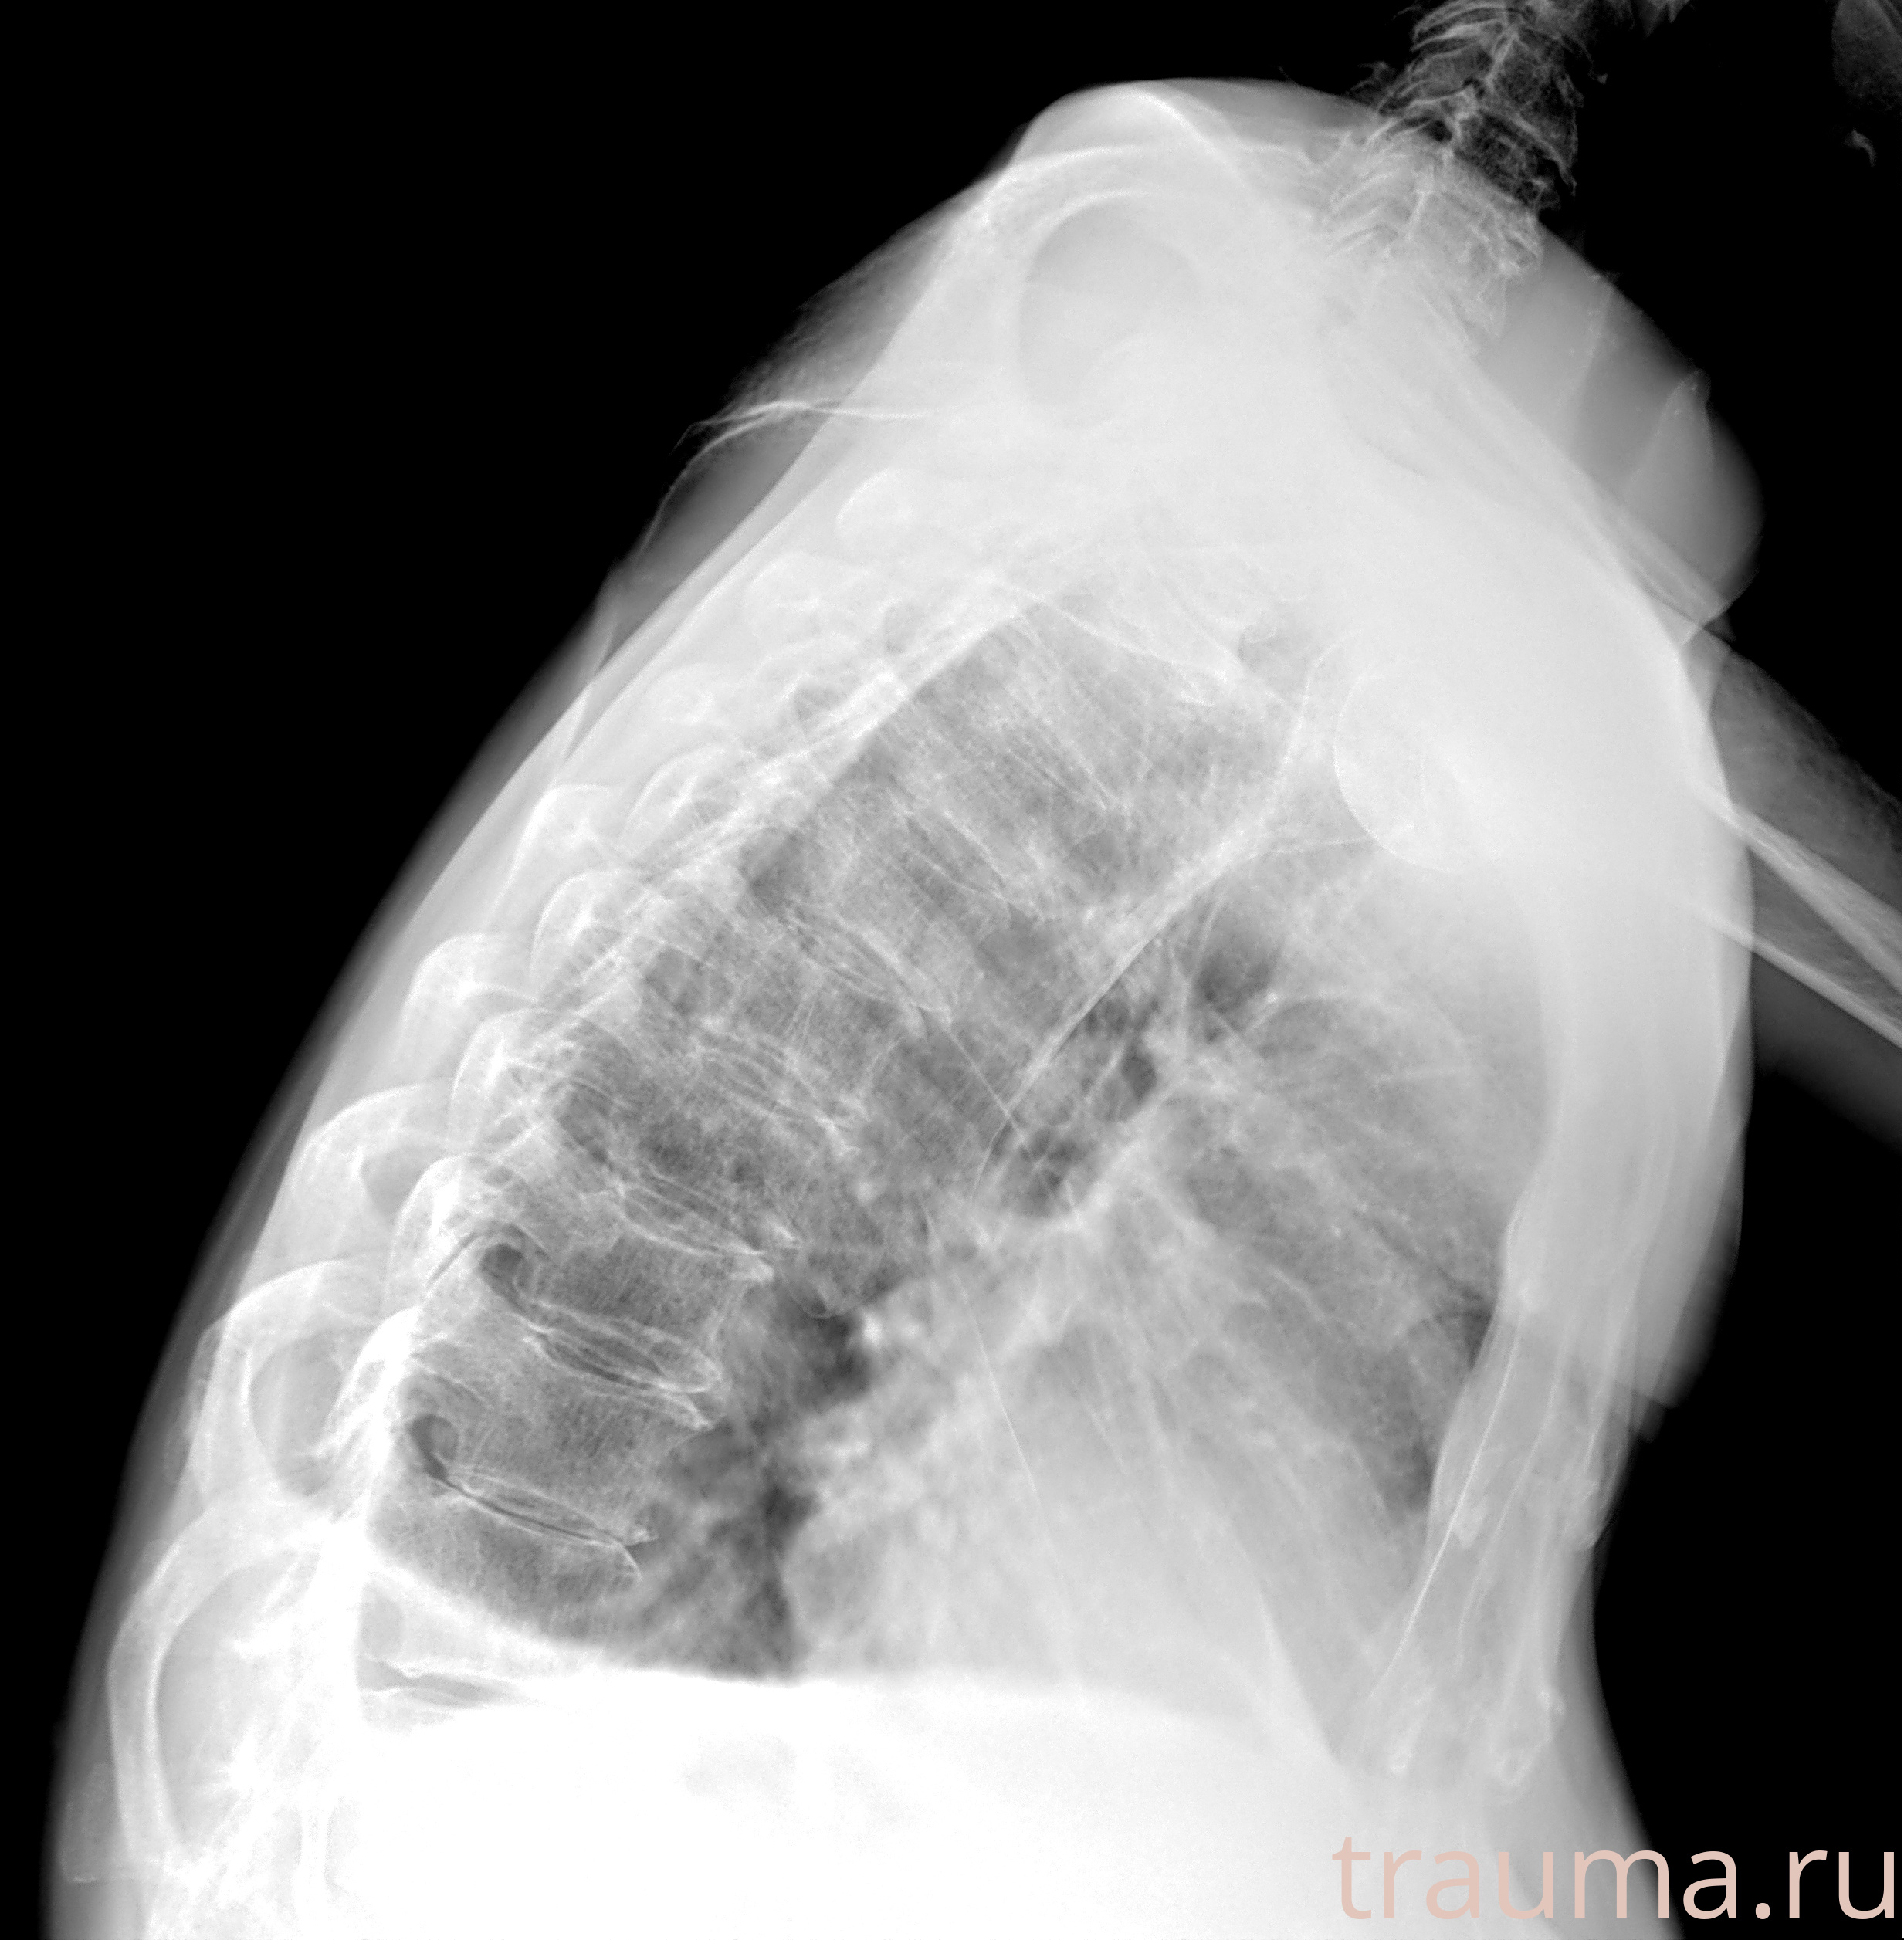

Рентгенограммы

Натуживание 26.12.2025 21:16:34